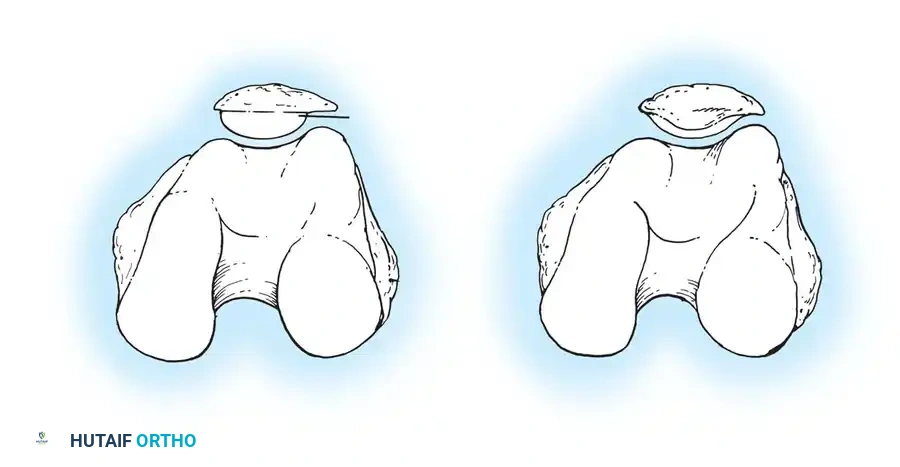

- The Surgical Transepicondylar Axis (TEA): Make the posterior femoral cut parallel to a line drawn between the prominence of the lateral epicondyle and the sulcus of the medial epicondyle.

- The Anteroposterior (AP) Axis (Whiteside's Line): Draw a line from the deepest part of the trochlear groove to the center of the intercondylar notch. The posterior femoral cut is made perpendicular to this axis.

- The Posterior Condylar Axis (PCA): When referencing the posterior condyles, the cut is typically made in 3 degrees of external rotation relative to a line connecting the most posterior aspects of the medial and lateral condyles.

⚠️ Pitfall: The Hypoplastic Lateral Condyle

In the valgus knee, the lateral femoral condyle is frequently hypoplastic. Relying solely on the posterior condylar axis in a valgus knee will lead to an internally rotated femoral component. In these cases, the TEA or AP axis must be prioritized.

- The Gap Technique: Using the cut surface of the proximal tibia, the posterior femoral cut is made parallel to the proximal tibial cut after the soft tissues have been balanced in extension.

Caution must be exercised when using the gap technique; reliance on ligaments that have stretched or contracted to nonanatomical lengths can lead to severe femoral component malrotation. The master surgeon cross-references multiple axes to ensure perfect rotational alignment.